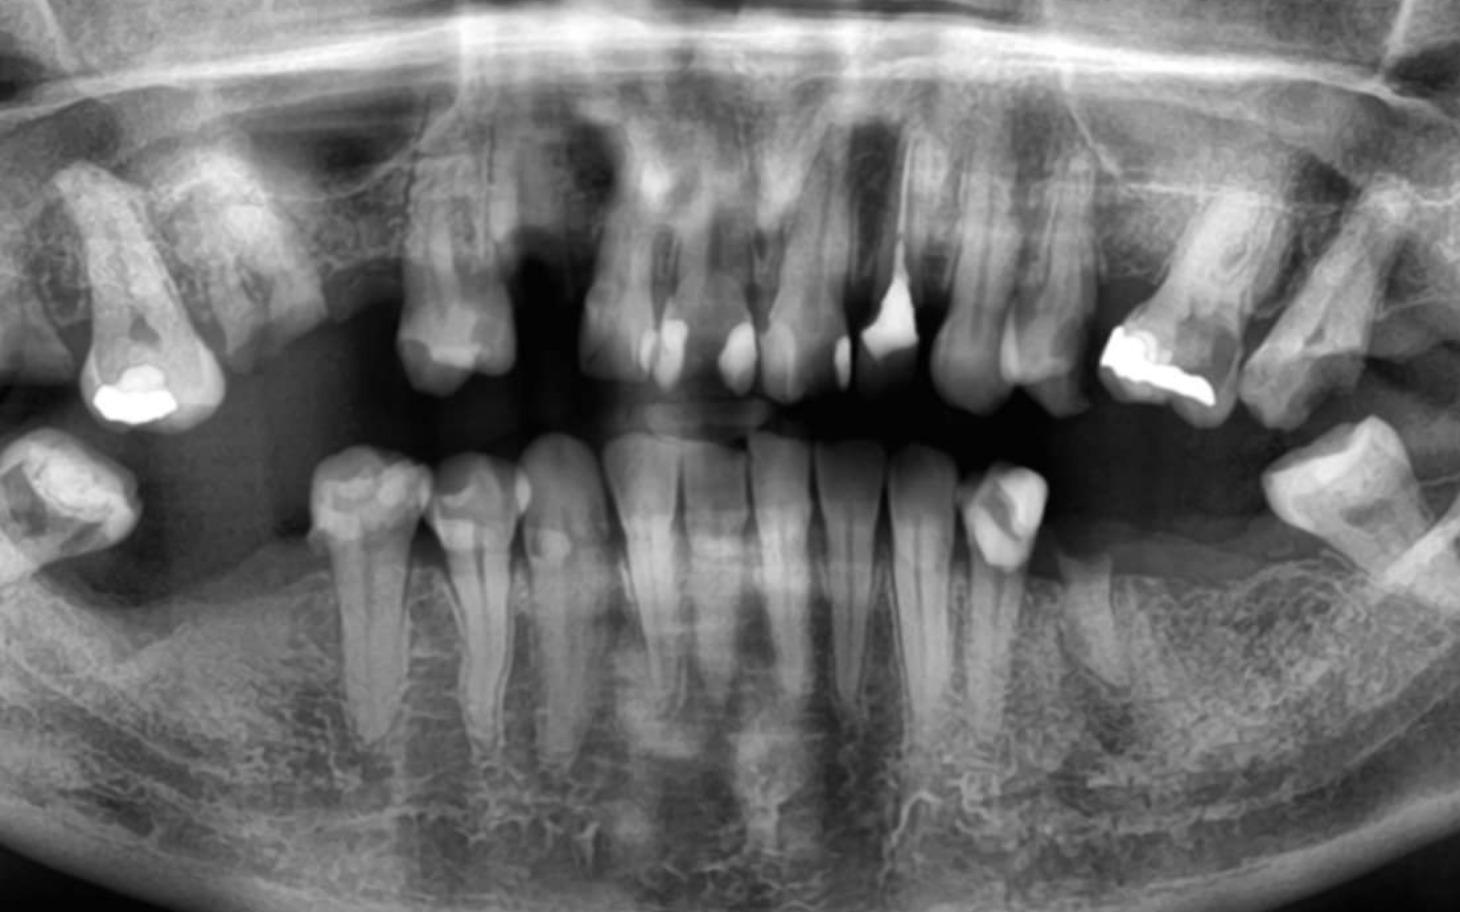

Miałam piękny zdrowy uśmiech który dodawał mi pewności siebie, przez źle dobrane leki zaczęły się strasznie psuć, kruszyć. Zaczęłam je tracić z prędkością światła,leczenia nie dawało żadnych skutków. Każdy zaleczony ząb się kruszył i został tylko korzeń.🥺 Na dzień dzisiejszy zostało ich nie wiele a ból z którym się zmagam jest nie do opisania. Przez braki w uzębieniu zaczęły się też problemy ze szczęka która po wyrwaniu ósemki zaczęła mi strzelać przy zwykłej czynności jak mówienie, nie mogę się uśmiechać nie mogę jeść a niedługo z powodu bólu przestanę mówić😥. Jedyny sposób na powstrzymanie moich problemów jest kosztowna operacja w klinice chirurgii szczękowej i wstawienie chociażby zwykłej protezy na które mnie nie stać.